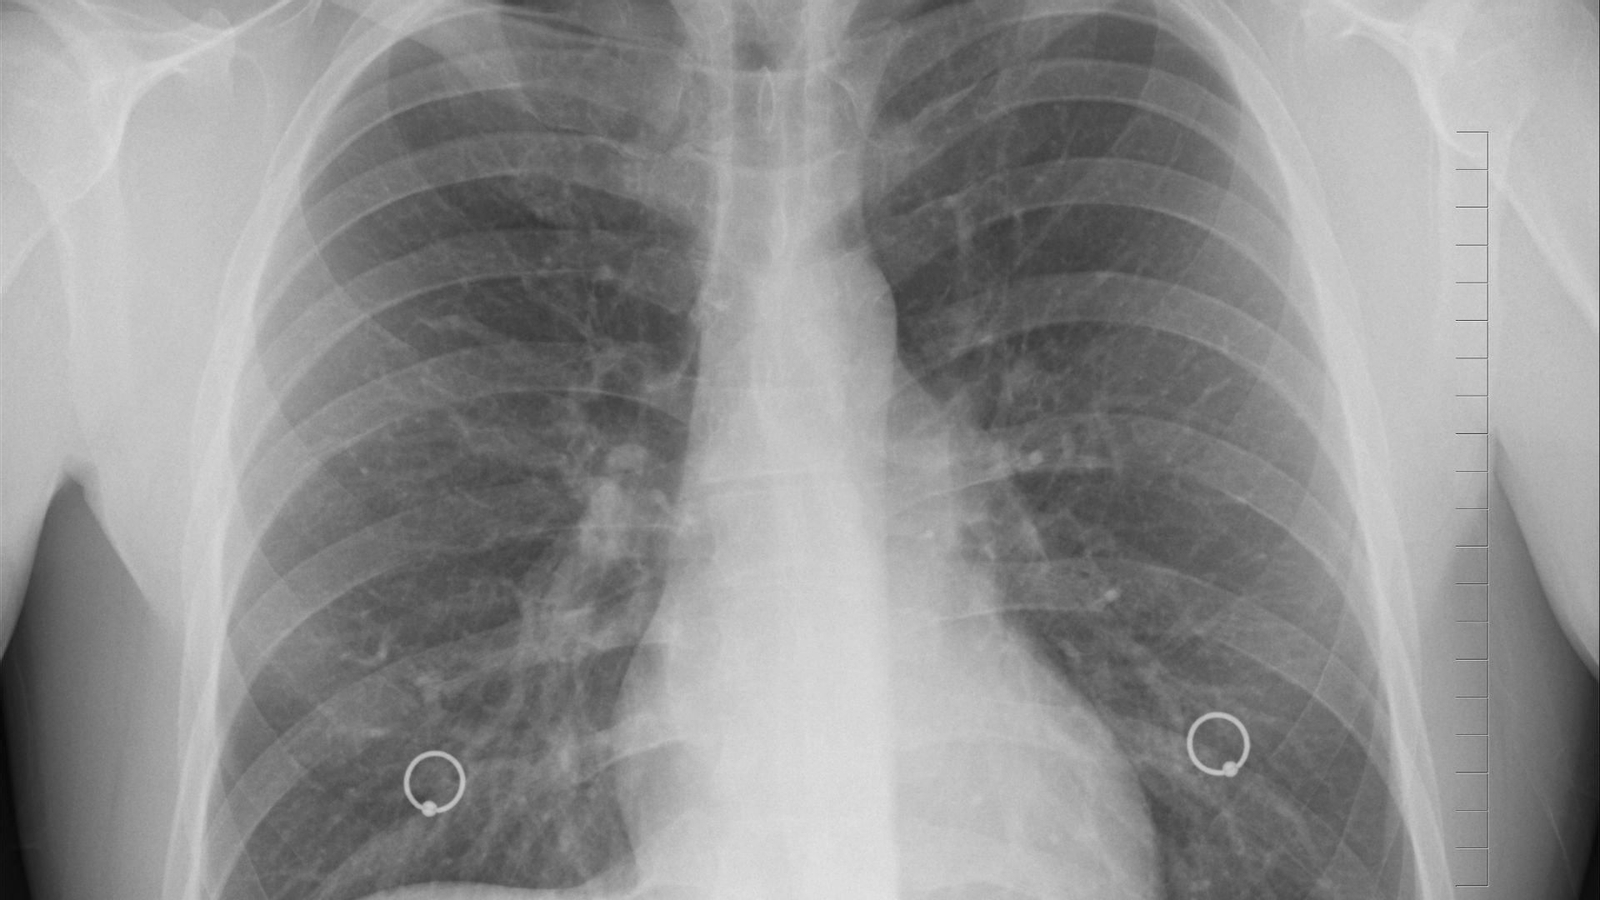

Aumentan los casos de cáncer de pulmón en los jóvenes y en las mujeres

El año pasado murieron 22.700 personas de cáncer de pulmón, siendo la primera causa de muerte por tumor, según el INE. El principal tumor torácicoes el carcinoma de pulmón de célula no pequeña, con 27.940 casos, seguido del carcinoma de pulmón de célula pequeña, que en un 70% de casos se diagnostica en estadios avanzados. Como principal factor de riesgo, destacan la “normalización” del tabaco, siendo el 40,5% de los afectados son fumadores habituales mientras que el 46,5% es exfumador. Solo un 11,5% de los pacientes reconoce no haber fumado nunca.